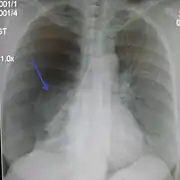

Chest X-ray

A plain chest radiograph, ideally with the X-ray beams being projected from the back (posteroanterior, or "PA"), and during maximal inspiration (holding one's breath), is the most appropriate first investigation.[30] It is not believed that routinely taking images during expiration would confer any benefit.[31] Still, they may be useful in the detection of a pneumothorax when clinical suspicion is high but yet an inspiratory radiograph appears normal.[32] Also, if the PA X-ray does not show a pneumothorax but there is a strong suspicion of one, lateral X-rays (with beams projecting from the side) may be performed, but this is not routine practice.[15][19]

It is not unusual for the mediastinum (the structure between the lungs that contains the heart, great blood vessels, and large airways) to be shifted away from the affected lung due to the pressure differences. This is not equivalent to a tension pneumothorax, which is determined mainly by the constellation of symptoms, hypoxia, and shock.[13]

The size of the pneumothorax (i.e. the volume of air in the pleural space) can be determined with a reasonable degree of accuracy by measuring the distance between the chest wall and the lung. This is relevant to treatment, as smaller pneumothoraces may be managed differently. An air rim of 2 cm means that the pneumothorax occupies about 50% of the hemithorax.[15] British professional guidelines have traditionally stated that the measurement should be performed at the level of the hilum (where blood vessels and airways enter the lung) with 2 cm as the cutoff,[15] while American guidelines state that the measurement should be done at the apex (top) of the lung with 3 cm differentiating between a "small" and a "large" pneumothorax.[33] The latter method may overestimate the size of a pneumothorax if it is located mainly at the apex, which is a common occurrence.[15] The various methods correlate poorly but are the best easily available ways of estimating pneumothorax size.[15][19] CT scanning (see below) can provide a more accurate determination of the size of the pneumothorax, but its routine use in this setting is not recommended.[33]